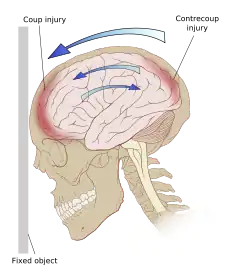

Ricochet of the brain within the skull may account for the coup-contrecoup phenomenon.[66]

Even in the absence of an impact, significant acceleration or deceleration of the head can cause TBI; however in most cases, a combination of impact and acceleration is probably to blame.[37] Forces involving the head striking or being struck by something, termed contact or impact loading, are the cause of most focal injuries, and movement of the brain within the skull, termed noncontact or inertial loading, usually causes diffuse injuries.[20] The violent shaking of an infant that causes shaken baby syndrome commonly manifests as diffuse injury.[67] In impact loading, the force sends shock waves through the skull and brain, resulting in tissue damage.[37] Shock waves caused by penetrating injuries can also destroy tissue along the path of a projectile, compounding the damage caused by the missile itself.[23]

Damage may occur directly under the site of impact, or it may occur on the side opposite the impact (coup and contrecoup injury, respectively).[66] When a moving object impacts the stationary head, coup injuries are typical,[68] while contrecoup injuries are usually produced when the moving head strikes a stationary object.[69]